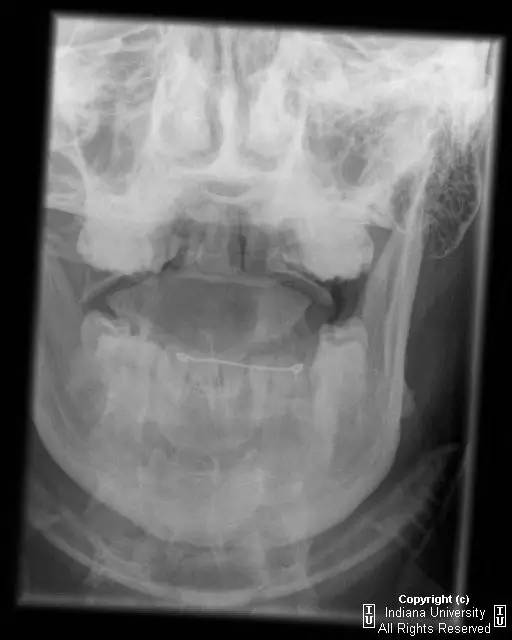

CR: C1侧块相对C2侧块外侧移位约5 – 6 mm,符合Jefferson骨折。椎体周围软组织明显肿胀。MR: 椎体周围间隙可见血肿。覆膜完整。寰枕前韧带断裂。寰枢前韧带完整。左侧横韧带从C1侧块的内侧分离,CT对应在C1侧块内侧见小撕脱骨折。翼状韧带完整。寰枕后韧带完整。前纵韧带和后纵韧带完整。黄韧带完整。

Jefferson骨折(Jefferson fracture)是前后弓均累及的C1环粉碎性骨折。Jefferson骨折为头顶受打击并轴向载荷的结果,力从颅骨经枕骨髁传递到颈椎,C1侧块在枕骨髁和C2上关节面之间被压缩,基于侧块的形状产生向心力而导致C1爆裂骨折。齿状突开口位或冠状位重建CT图像应仔细观察双侧C1和C2关节侧块间有无偏移。虽然C1侧块相对C2上关节面侧方移位提示存在骨折,但在X线片上有时难以发现骨折线。MR可显示相应的韧带损伤。

警告:C1异常时单侧或双侧寰枢椎侧方偏移可达2 mm,而Jefferson骨折通常偏移3 mm或以上。

Jefferson骨折。A,侧位片示C1后弓骨折线(箭)。B,开口位示C1侧块相对于C2偏移(箭)。C和D,轴位CT图像示骨折线通过C1环前、后部(箭)。E,冠状位CT图像示翼状韧带小的撕脱骨折(黑箭)。此图像上也标注了C1在C2上方偏移(白箭)。